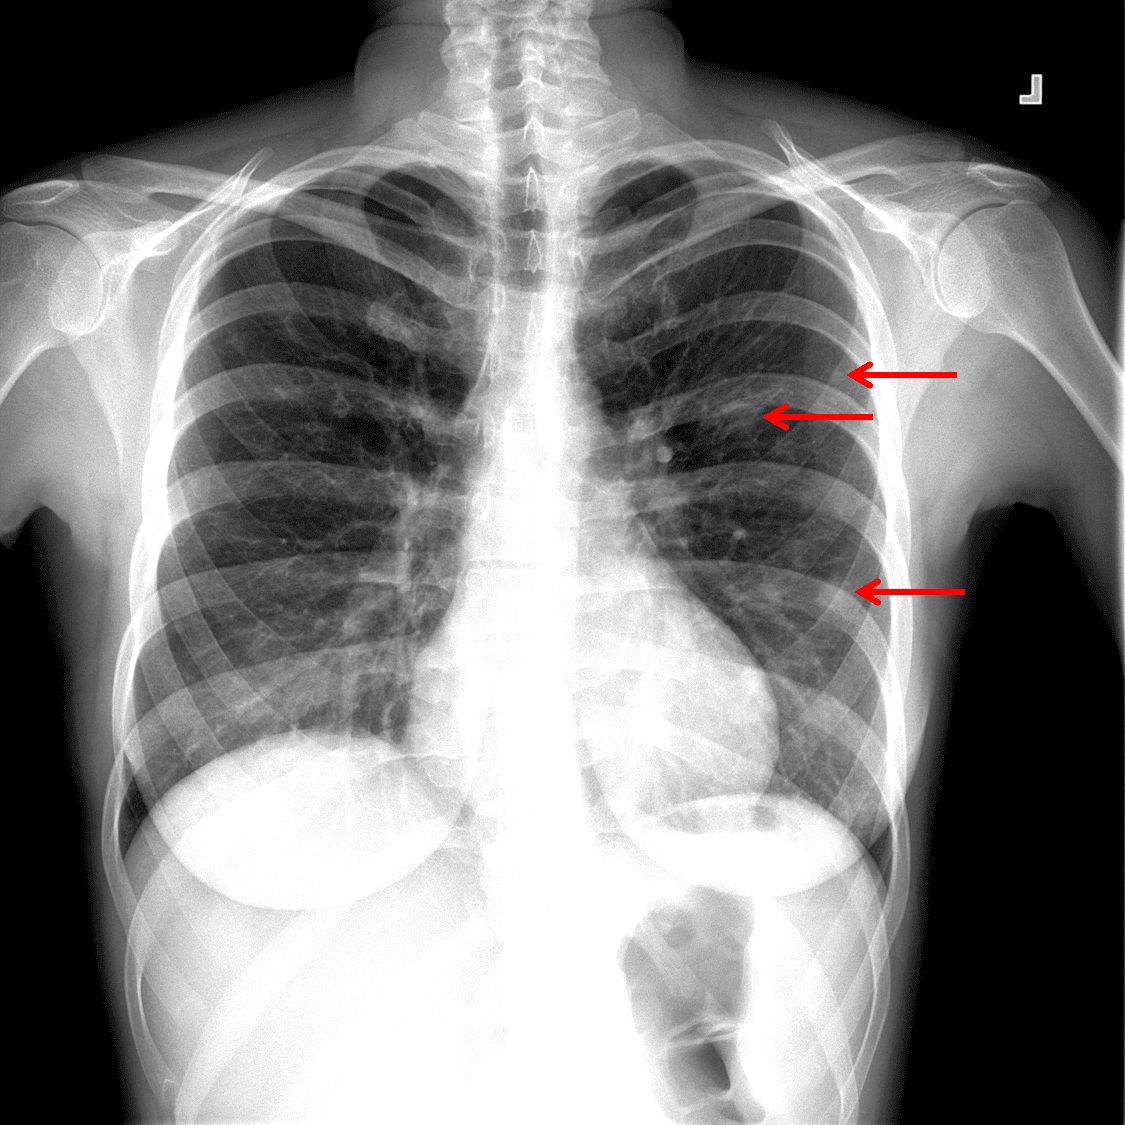

Chest radiograph

Sample ReportAcute bilateral subsegmental pulmonary thromboembolism without CT evidence for right heart strain. In combination with the finding of scattered bilateral peripheral cavitary pulmonary nodules, this raises concern for septic embolic disease.

Mild dependent atelectasis and trace bilateral pleural effusions.